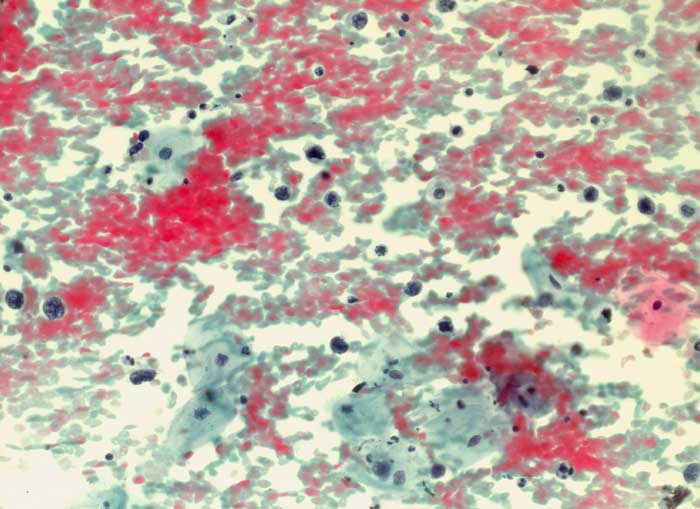

PathoPic ID 6270 - diffuses grosszelliges B-Zelllymphom

diffuses grosszelliges B-Zelllymphom

maligner Tumor

Portio

Genitalorgane, weiblich

Portioabstrich: Auf blutigem Hintergrund einzeln liegende nacktkernige

Lymphomzellen und

Apoptosen. Zellverbände oder organoide Strukturen fehlen. Ausserdem sieht man

Plattenepithelien vom intermediären und superfizialen Zelltyp.

Autopsie: Generalisiertes diffuses grosszelliges B-Zell Lymphom

St.n. Non Hodgkin-Lymphom. Rezidiv iliacal rechts.

Zytologische Diagnose: Hochgradig atypische lymphoide Elemente. Befund vereinbar mit malignem grosszelligem Lymphom.

200